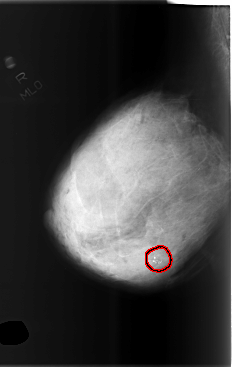

C_0505_1.RIGHT_MLO

RIGHT_CC LINES 5800 PIXELS_PER_LINE 3936 BITS_PER_PIXEL 12 RESOLUTION 50 OVERLAY

RIGHT_MLO LINES 5872 PIXELS_PER_LINE 3704 BITS_PER_PIXEL 12 RESOLUTION 50 OVERLAY

FILE: C_0505_1.RIGHT_MLO.OVERLAY

TOTAL_ABNORMALITIES 1

ABNORMALITY 1

LESION_TYPE CALCIFICATION TYPE DYSTROPHIC DISTRIBUTION CLUSTERED

ASSESSMENT 4

SUBTLETY 5

PATHOLOGY BENIGN

TOTAL_OUTLINES 1

BOUNDARY